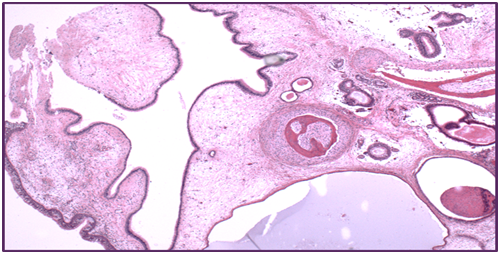

A 66 year old woman presented to the department of otolaryngology with complains of chronic headaches, rightnasal obstruction, and midfacial pain with a duration of 3 years. Clinical examination with a rigid endoscope revealed a polypoidal mass like structure in the right nasal cavity, extending from the middle turbinate to the posterior nasal space. CT and MRI depicted a soft tissue mass with calcification developing in the right nasal cavity, with no signs of bone erosion. The mass had a cephalocaudal diameter of 5 cm and a maximum anterior-posterior diameter of 3 cm extending from the level of the middle and superior turbinate back to the nasopharynx occluding partly the sphenoid sinus ostium. The maxillary and frontal sinuses were unremarkable. The patient underwent functional endoscopic sinus surgery with complete tumor resection. During surgery a small specimen was sent for frozen biopsy histopathological examination in order to exclude evidence of malignancy. Postoperative course was uneventful. The submitted specimen had a smooth hard surface with small irregular fragments of soft and bony tissue. Microscopic evaluation revealed an epithelial component consisting of islands of respiratory type epithelium with polypoid configuration forming invaginations into the subepithelial loose fibrovascular myxoid stromaadmixed with areas of immature fibrocartilaginous and bony tissue. No atypia or mitoses were observed or signs of infiltrative growth, excluding malignancy (Figure1 & 2).

Figure 1 Polypoid configuration Respiratory type epithelium with invaginations into the lamina propria Cystic dilated spaces lined by mucus-secreting cells and hyperplastic seromucinous glands.